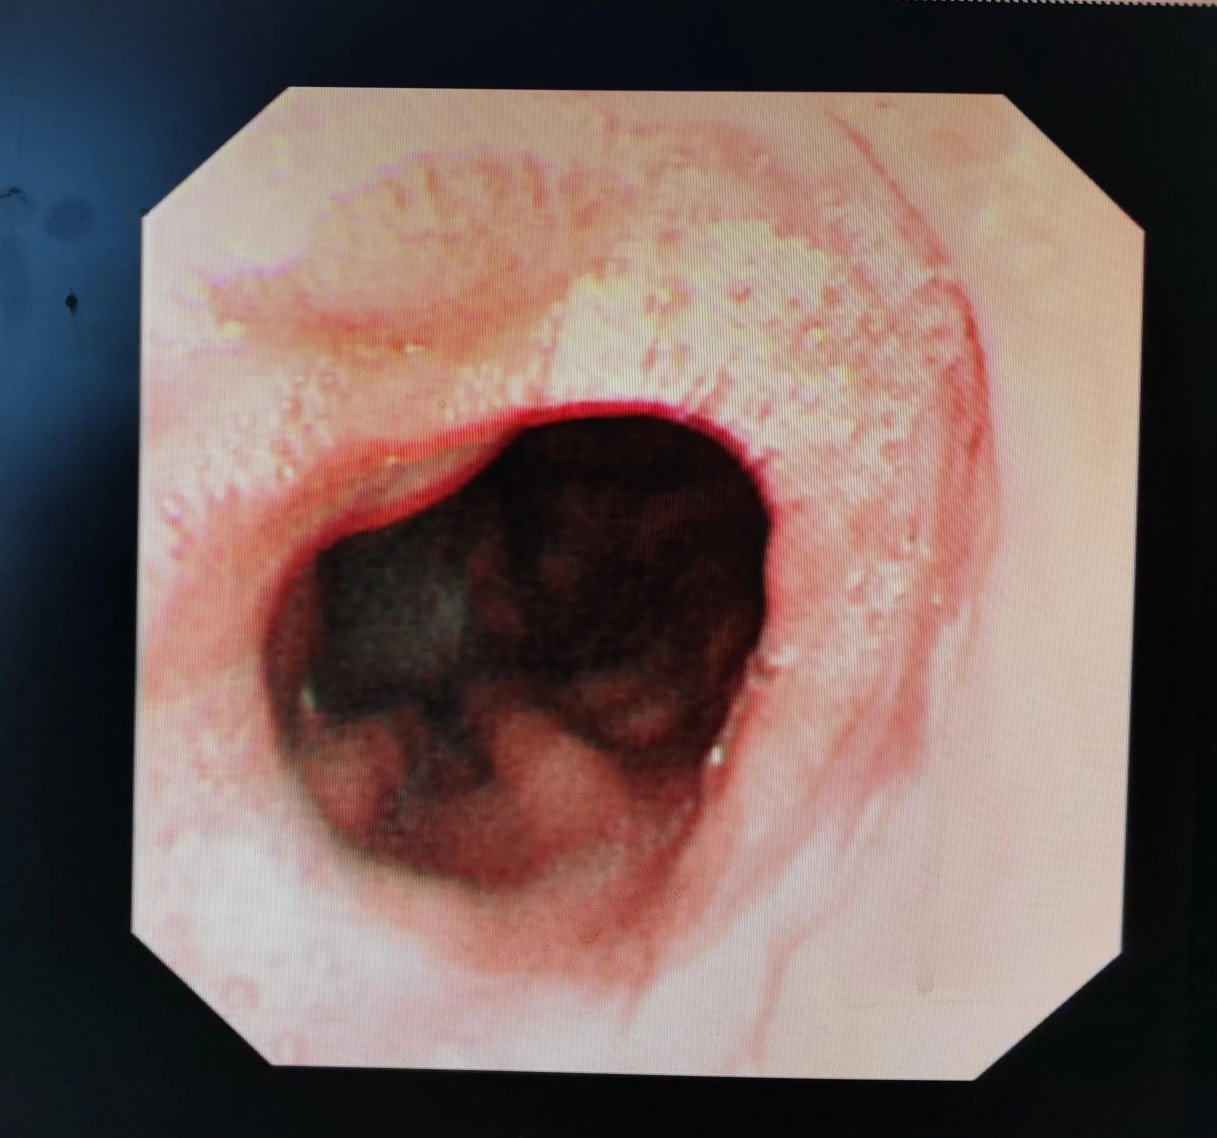

胃镜下看到的贲门肿瘤

从食管向胃方向看到的贲门肿瘤

贲门肿瘤已经快完全堵塞食管了